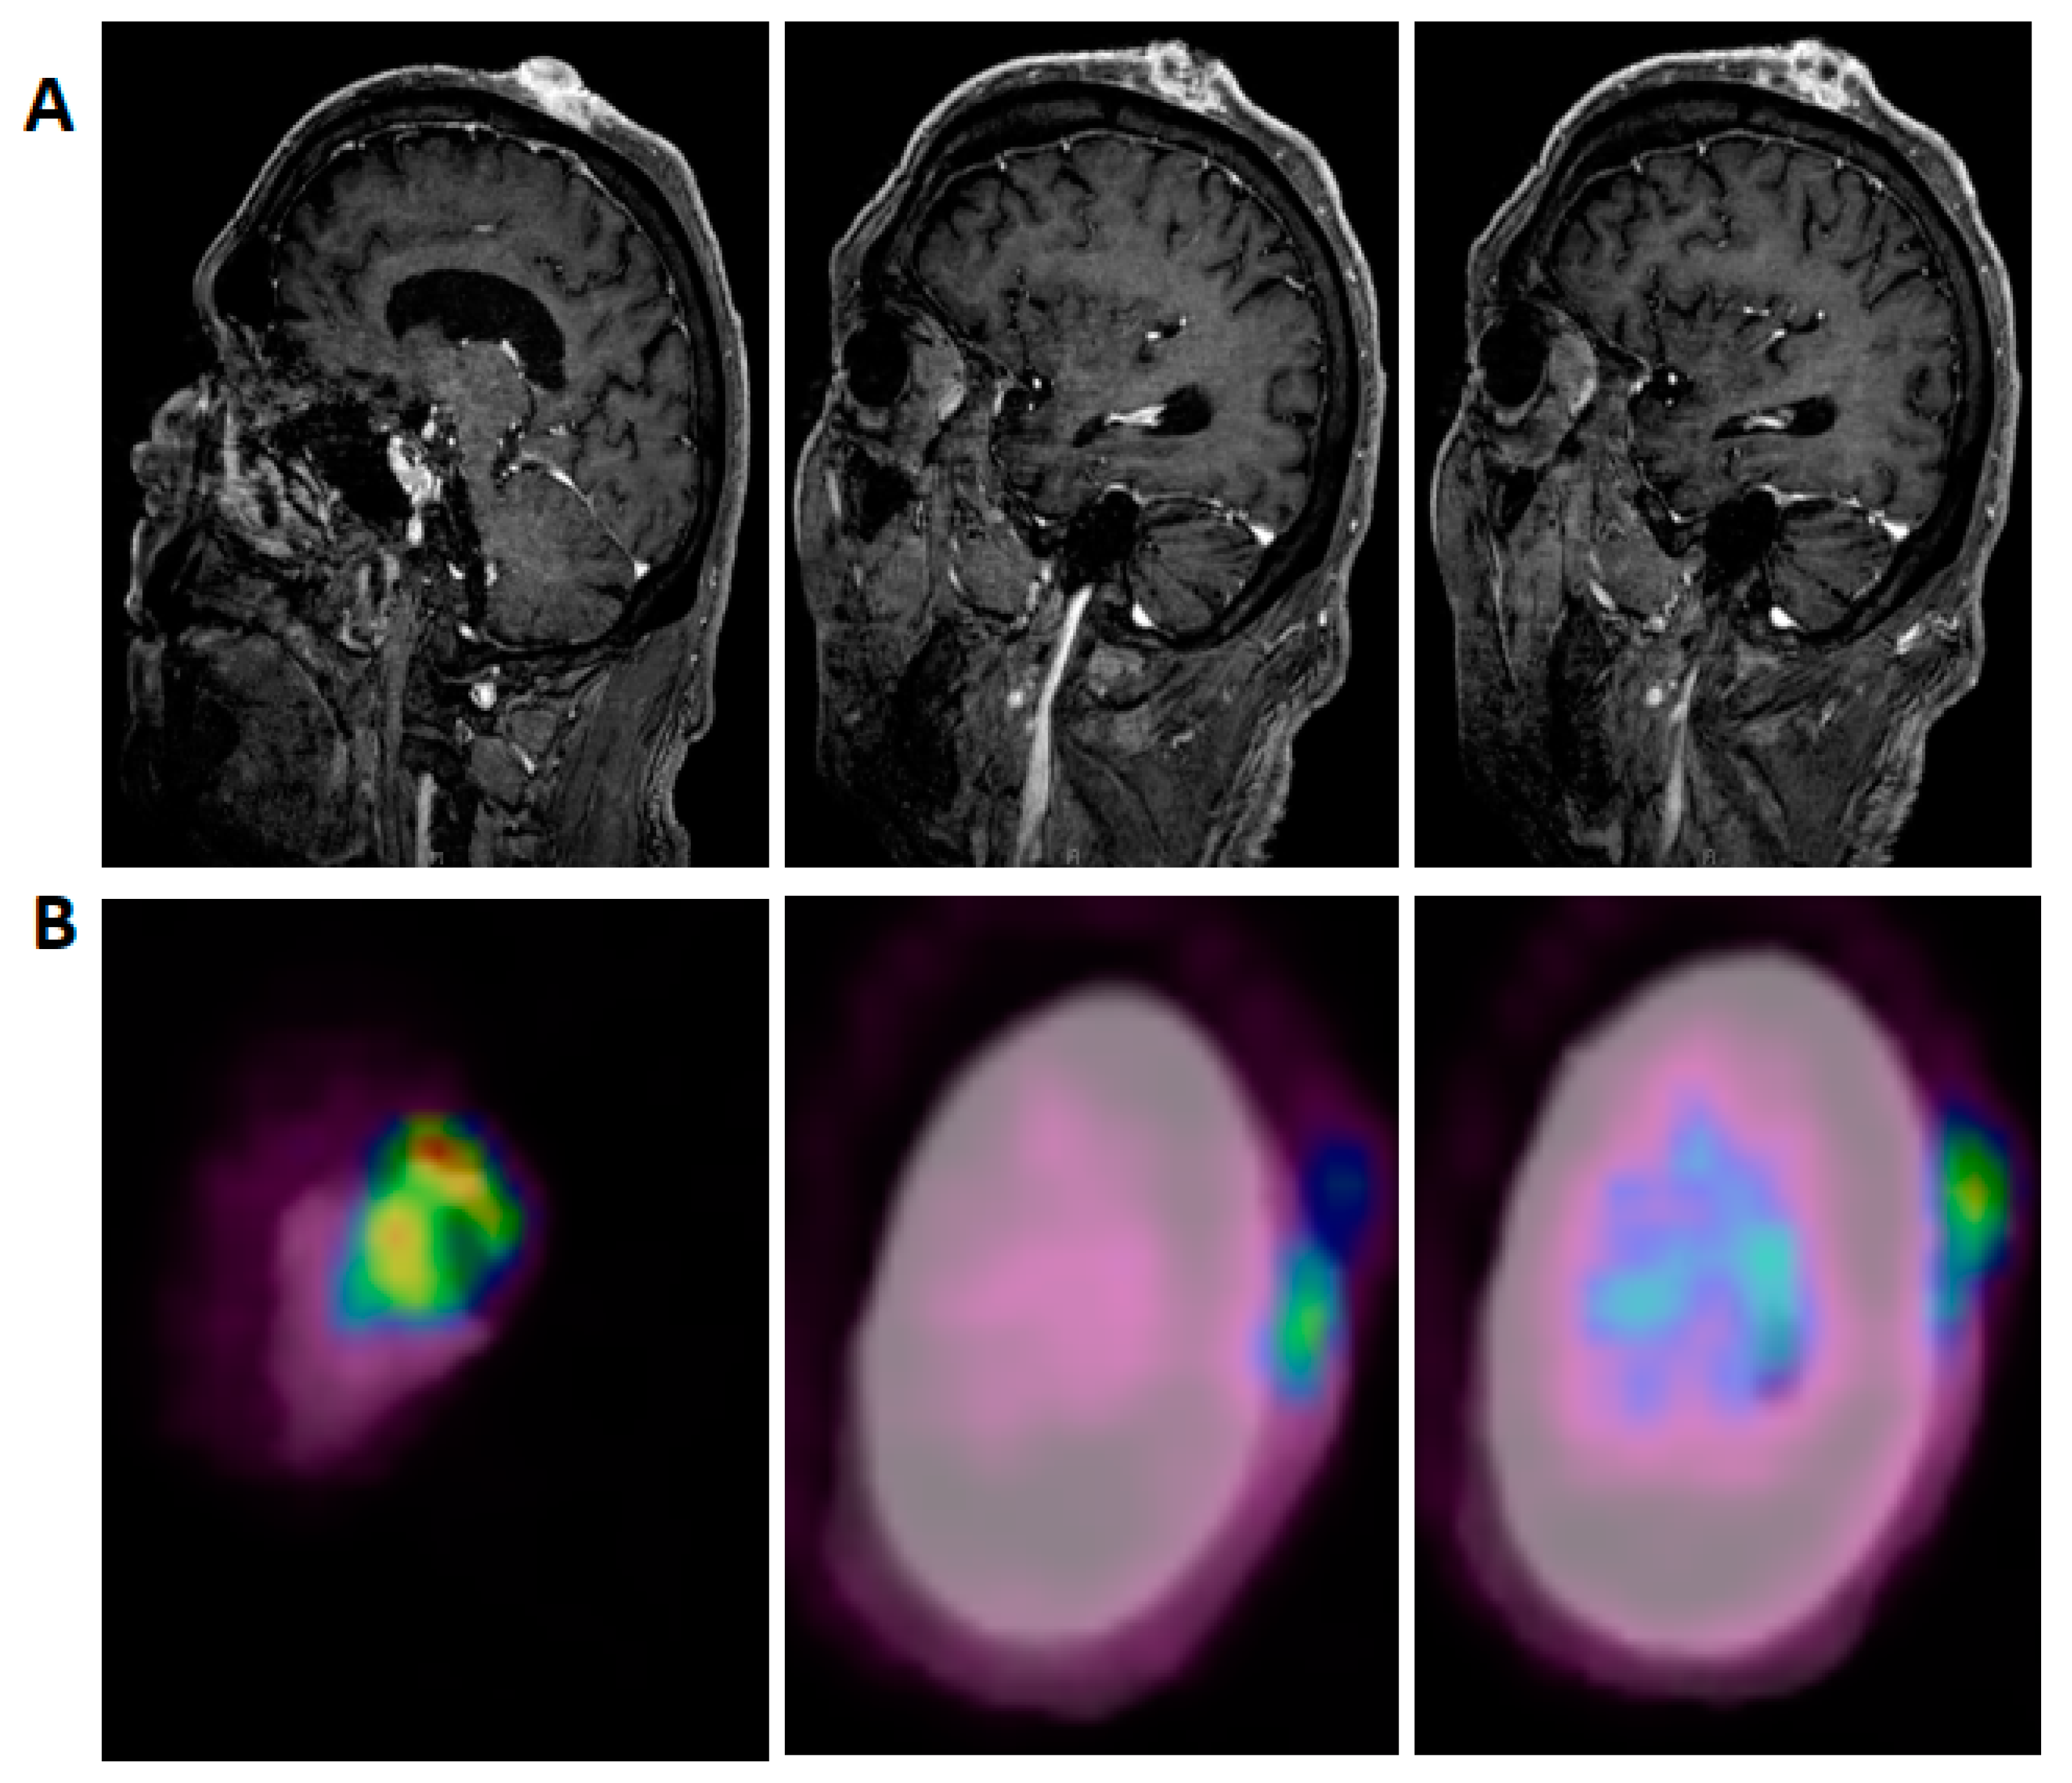

The patient had extensive local SCC involving the majority of his scalp, with no evidence on examination or imaging for either regional or metastatic disease. MRI of the brain and neck was done and showed irregularly enhancing scalp lesions without evidence of adjacent osseous or intracranial extension (largest lesion was 4.7 cm by 3.4 cm (Figure 1A)). PET/CT was significant for fluorodeoxyglucose (FDG) avid soft tissue masses in the left scalp, consistent with the patient’s known malignancy (standardized uptake value, SUV up to 4.7 (Figure 1B)). After tumor board discussion, decision was made for surgical resection; he underwent radical resection including full thickness resection of his scalp, and removal of the underlying external cortex of his calvarium, with placement of a collagen/glycosaminoglycan allograft to encourage granulation in preparation to receive a split thickness skin graft. Pathology showed a moderately differentiated SCC with negative margins (the closest, deep margin was 2 mm); size was 8.3 cm, depth of invasion was 1.1 cm; perineural invasion was identified. Within four weeks since resection, the patient developed extensive dermal metastasis surrounding the resection bed, which on biopsy were confirmed to be poorly differentiated CSCC.

Figure 1.

Representative pre-treatment, post-contrast, T1-weighted, sagittal MRI images (A) and fused PET-CT images (B) show disease extension predominantly from the vertex scalp to the left lateral temple region.